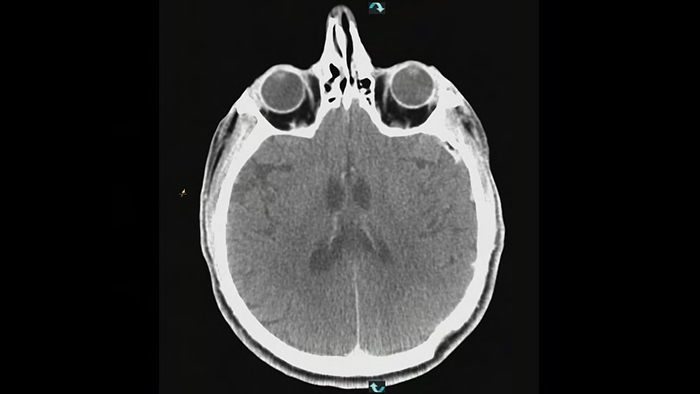

SmartCT Soft Tissue est une technique d’acquisition radiographique qui génère une visualisation de type TDM des tissus mous par rapport à d’autres structures au cours des procédures. Vous pouvez utiliser les images de type TDM pour évaluer les tissus mous après une MAV afin de vérifier le résultat final et les saignements potentiels lorsque le patient est encore sur la table.

La technologie ClarityIQ réduit la dose administrée au patient de 75 % en angiographie cérébrale par soustraction numérique*, tout en conservant une qualité d’image équivalente, par rapport à un système sans ClarityIQ pour prendre en charge une vaste population de patients. La fonction de compensation automatique des mouvements de la technologie ClarityIQ corrige les artefacts de mouvement et du crâne, ce qui est essentiel lors du placement de petits dispositifs à la base du crâne.

La technologie ClarityIQ réduit la dose administrée au patient de 75 % dans les procédures d’angiographie cérébrale par soustraction numérique (ASN),1 par rapport à un système sans ClarityIQ et ce, avec une qualité d’image équivalente. Sa fonction de compensation automatique des mouvements corrige les artefacts de mouvement et du crâne, ce qui est essentiel lors du positionnement de petits dispositifs à la base du crâne.